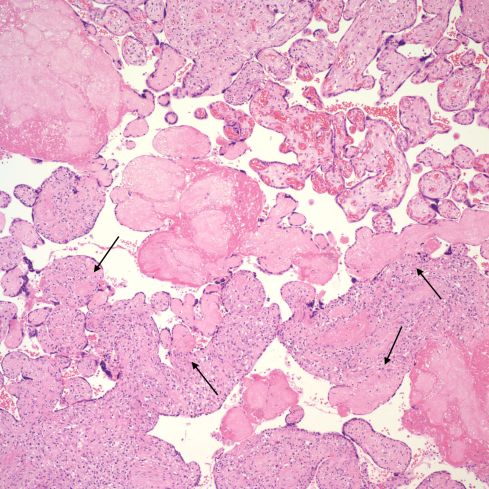

There is loss of identifiable capillaries and the villi show a progression to scarred, avascular villi (Fig 20, 21).

Fig 20) This intermediate magnification image shows a visually plausible a progression from VUE to avascular villi. (H&E, 20x)

Fig 21 This intermediate magnification shows a band of avascular villi cutting diagonally across the center of the field. There are also avascular villi that appear attached to villi with VUE (arrows). These small avascular villi often still have syncytiotrophoblast over the surface. They may all be the result of a collision of two separate events, with an early fetal vascular occlusion and a more recent VUE, or they may show progression from VUE to avascular villi. Even if they are separate events the avascular villi could still be a consequence of earlier VUE.

VUE is not restricted to terminal and intermediate villi, but can appear in larger stem villi (Fig 22,23).